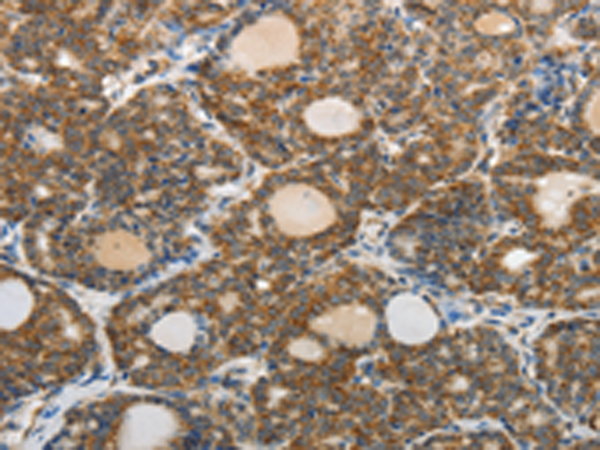

分类: 科研抗体货号: P04280别名: AT2; ATGR2; MRX88应用: IHC反应种属: Human, Mouse, Rat